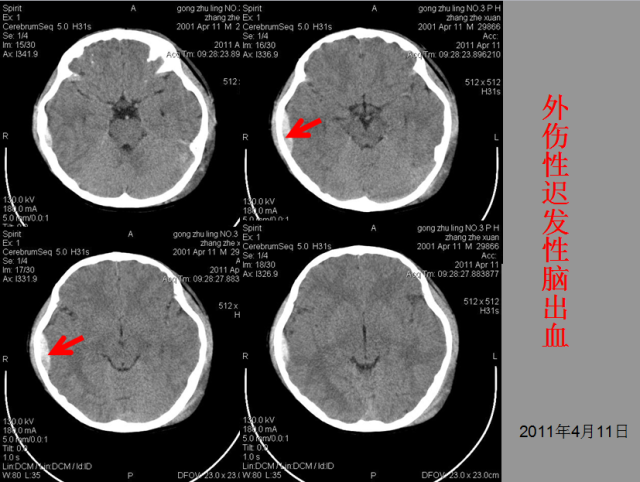

急性颅脑损伤篇

03

急胸症篇